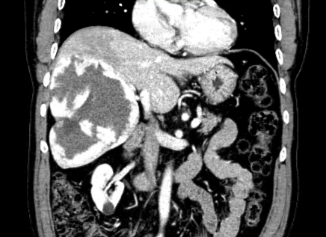

Early diagnosis of a hepatoma (also called primary liver cancer, hepatocellular cancer, or HCC) gives the best chance of long term survival. Patients needing routine liver cancer surveillance are: 1) all patients with cirrhosis, and 2) patients with hepatitis B infection and detectable virus growing in their blood. The most common causes of cirrhosis in the United States are hepatitis C and/or B infection, alcohol over use, and fatty liver. Unfortunately, 7 out of 10 patients with liver cancer have advanced cancer when found and will not benefit from surgical removal or liver transplant.

The most common cancer to the liver is metastatic from the colon or rectum. Surgical removal of cancer in the liver from the colon or rectum gives patients a 30-35% chance of being alive 5 years after surgery. Without surgery, most patients die within 12-18 months after diagnosis. Predictors of outcome include tumor size greater than 5 centimeters, having more than one tumor, having positive lymph nodes at the initial colorectal surgery, having a CEA greater than 200, and time between original colorectal surgery and development of metastatic tumor in liver less than 1 year. A patient without any of these risk factors has about a 7 out of 10 chance of being alive in 5 years. As a patient has more risk factors, their chance of surviving decreases. If a patient has all 5 risk factors, they have a 1 out of 10 chance of being alive in 5 years.